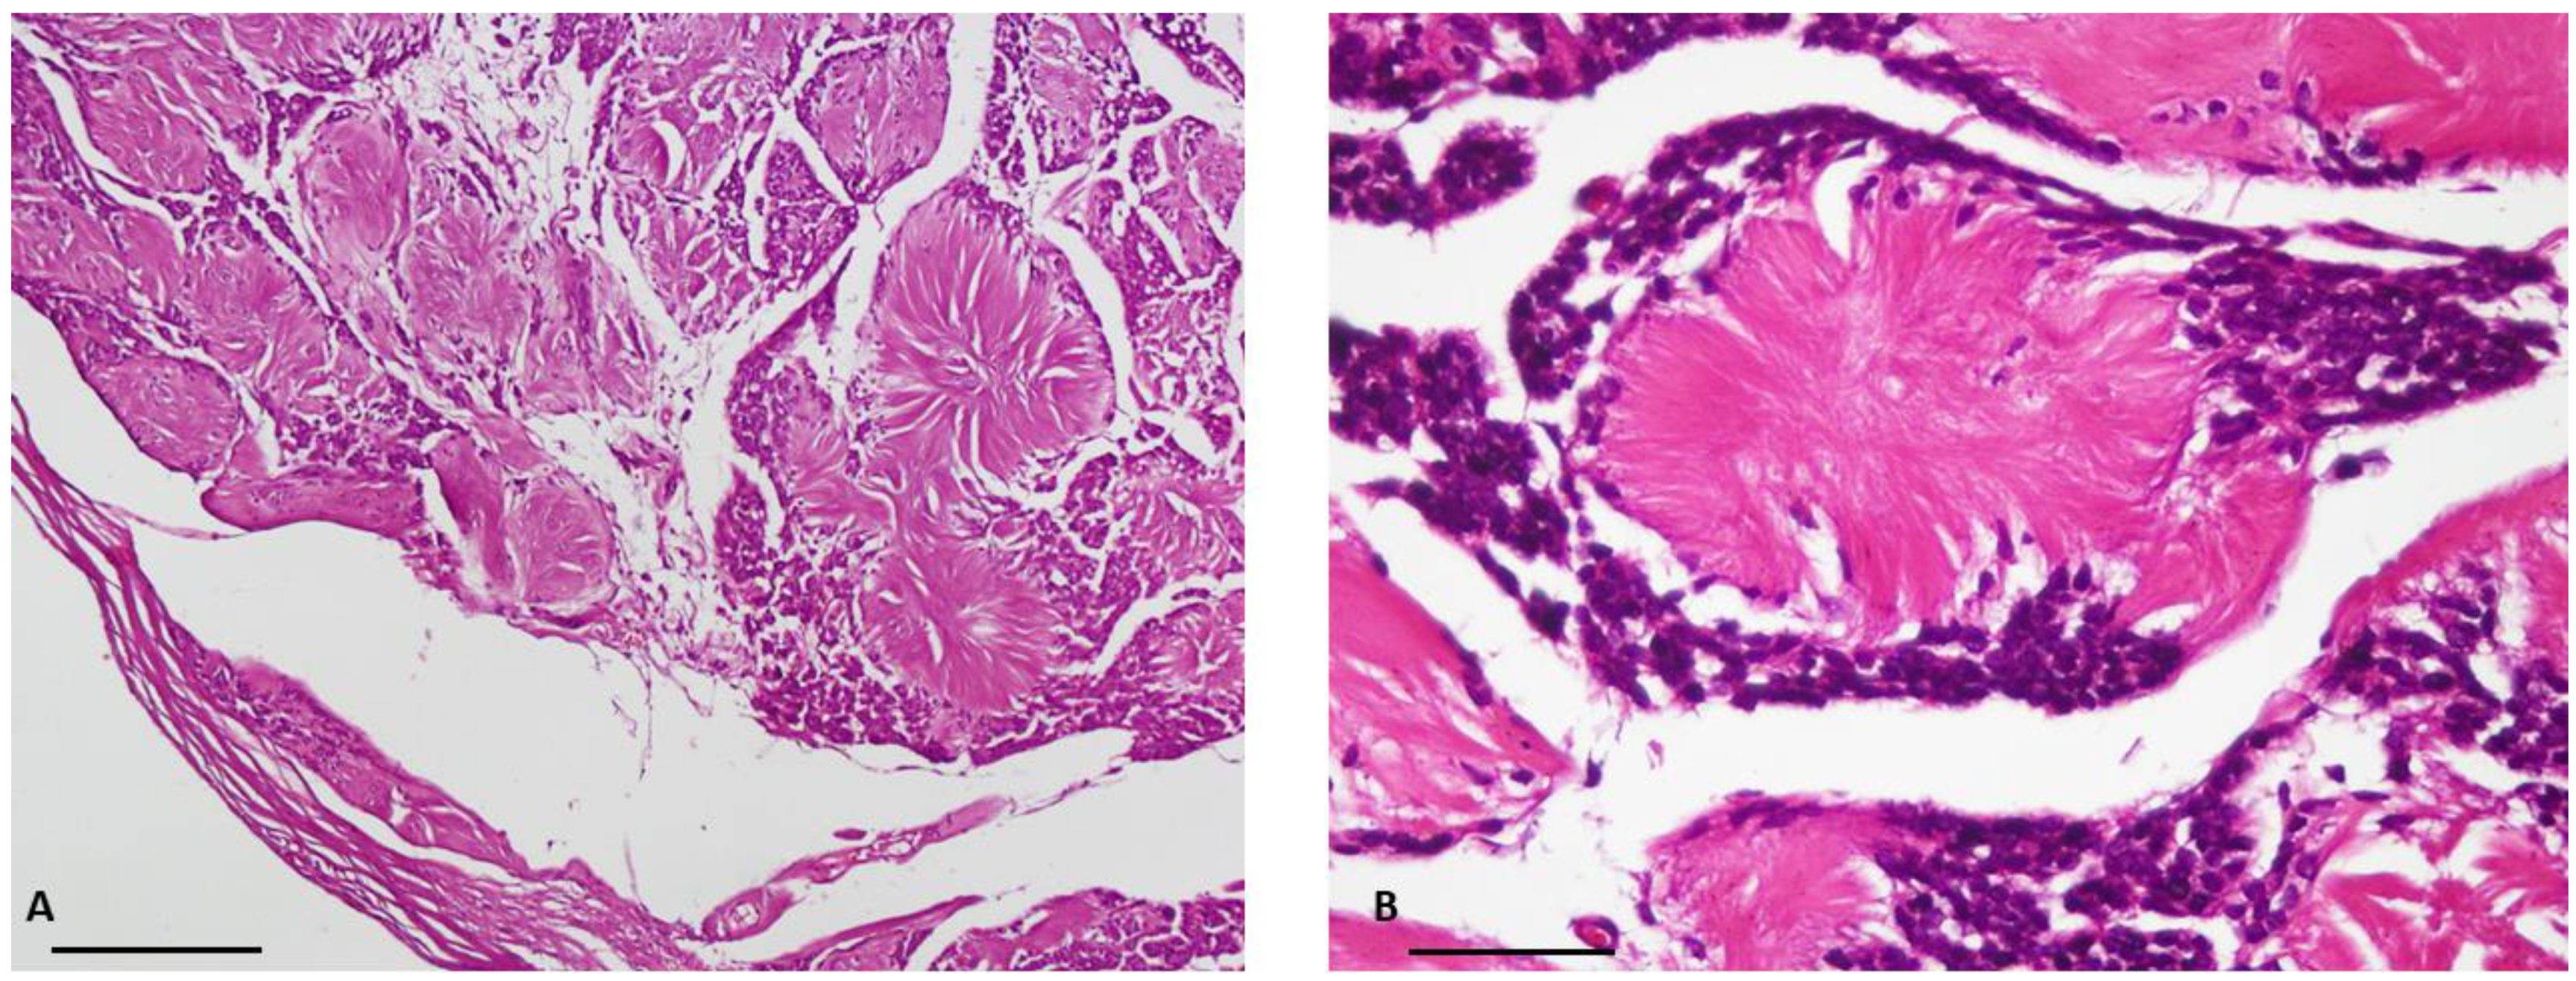

Figure 4. Negative immunostaining of tumor cells with Synaptophysin. (10× objective lens, scale bar = 100 μm).

Masson’s trichrome staining confirmed that the central core of the rosettes was composed of collagen fibers. Subsequent immunohistochemical study revealed diffuse expression of S100 protein (as the most commonly used marker to detect tumoral cells) [6] in the tumoral cells, confirming the Schwann cell origin of the tumor (Figure 1 and Figure 2). Additionally, staining for the neural markers showed focal positive expression for Neuron Specific Enolase (NSE) and negative for synaptophysin which confirmed our diagnosis (Figure 3 and Figure 4).

Immunohistochemical methods helped us to reach a definite diagnosis. Indeed, in our case, the tumor cells were strongly and diffusely positive for S100 protein and focally positive for NSE. Neuroblastoma-like schwannoma showed focal areas with typical immunophenotyping of conventional schwannoma and all tumor cells were strongly and diffusely positive for S100 protein, but typically negative for other markers of neural differentiation, such as synaptophysin [3]. However, there are reports in which the tumor cells show positivity for other neural markers such as NSE [9].